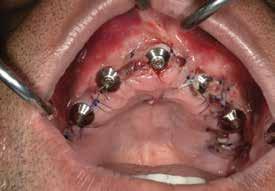

72 FDC 2026 Speaker: Full Arch Implant Reconstruction in the Digital Era: Past, Present and Future